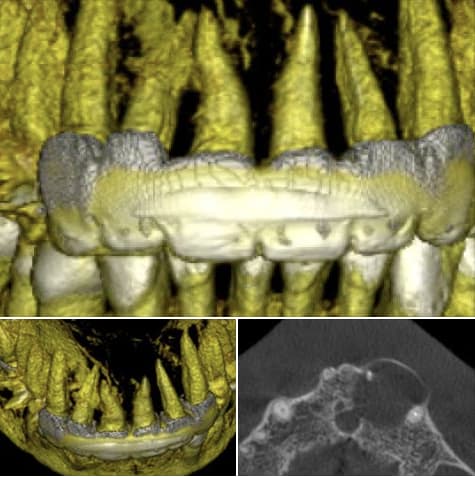

03_gazette_3-14_FM_Müller_Implants_dentaires_gavk9q.pdf